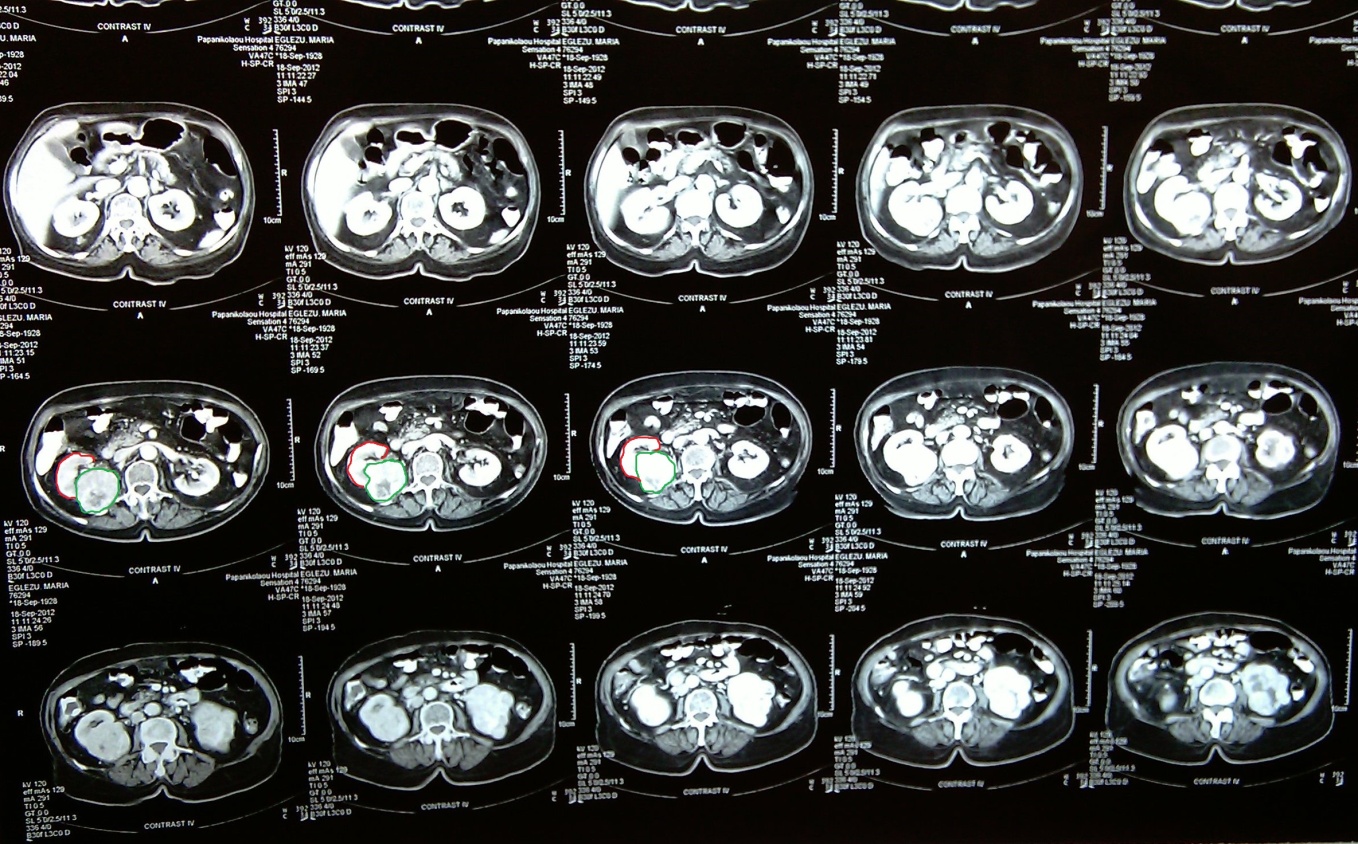

Evident dilation of the left ureter -- yellow outline. Green outline -- Chordoma (Courtesy Dr. V. Penopoulos)